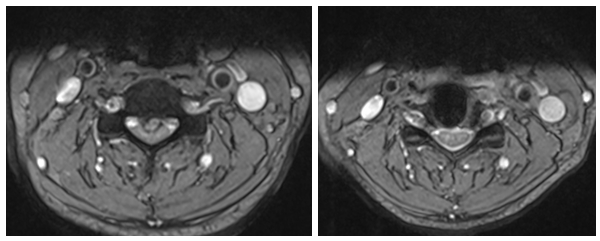

劉女士家屬知道惠州市第三人民醫(yī)院有個(gè)專治頸肩腰腿疼痛的科室,即來頸肩腰腿痛門診就診,入院后MRI示:頸3/4椎間盤變性并向后下脫出,頸3/4-6/7水平椎管狹窄及雙側(cè)神經(jīng)根受壓,以頸3/4水平狹窄為著。

術(shù)前MRI 和術(shù)后MRI